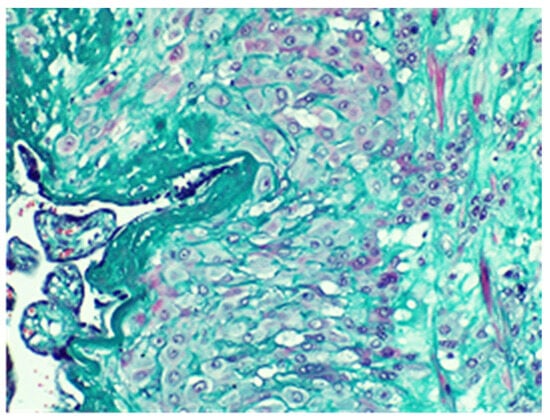

Figure 8.

Placenta with aspects of accretion-muscle fibers colored in red on the right of the image, Van Gieson stain, × 20.